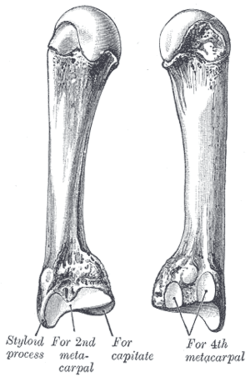

Carpometacarpal bossing (or metacarpal/carpal bossing is a small, immovable mass of bone on the back of the wrist. The mass occurs in one of the joints between the carpus and metacarpus of the hand, called the carpometacarpal joints, where a small immovable protuberance[1] occurs when this joint becomes swollen or bossed.

The joint between the index metacarpal and the capitate is a fibrous non-mobile joint. Some people have a gene that leads to this growth. It looks like arthritis (bone spurs on each side of the joint) on X-ray. It looks like a ganglion on the hand, but more towards the fingertips.

The carpometacarpal joint is usually found at the base of the second and third metacarpal bones at the point where they meet the small bones of the wrist.[2]